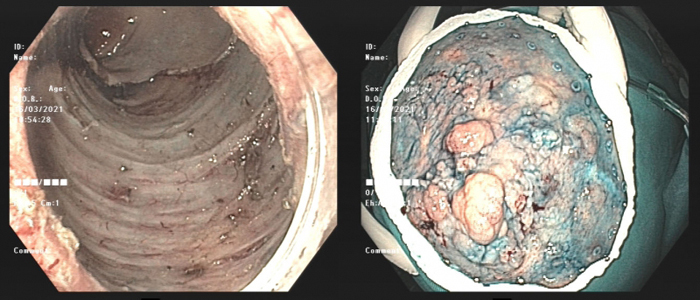

Hình ảnh nội soi đường tiêu hóa phát hiện đám tổn thương dạng u ống tuyến lan tỏa tại trực tràng. Tổn thương chiếm 2/3 chu vi trực tràng lan xuống ống hậu môn.

Hình ảnh các khối sùi lớn ken đặt lòng trực tràng (ảnh phải) và hình ảnh sau khi được cắt bỏ